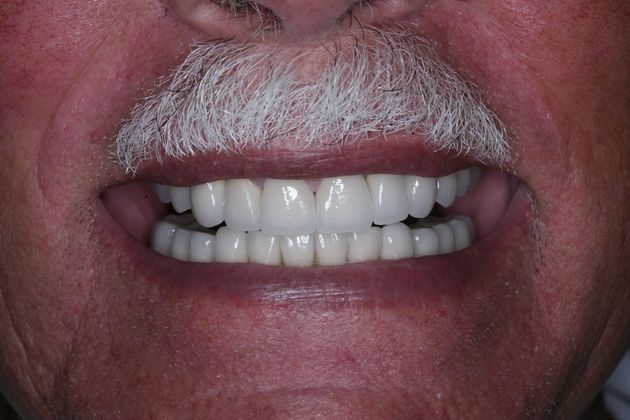

Procedures; orthodontics, gum repositioning, implant revision and new implant placement, root canal, full mouth reconstruction with crowns and implant retained crowns, bite guard therapy.

This patient wanted his smile to look better. He had a severe life long grinding habit that decimated his teeth, causing fractures, tooth loss and collapse of his bite. He wanted the best possible outcome. His was a complicated treatment that required the coordination of treatment of several specialists, much patience on his part, and resulted in an impressive result.